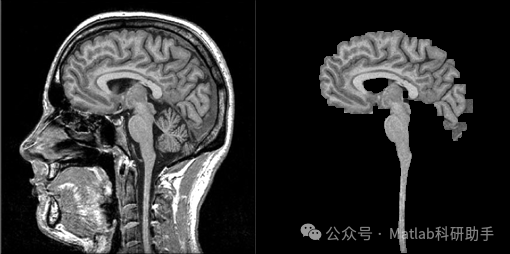

头骨剥离(Skull Stripping)是医学图像处理中的一个关键预处理步骤,旨在从脑部MRI或CT图像中精确分离出脑实质,去除头骨、皮肤、肌肉等非脑组织。这一过程对于后续的脑疾病诊断、体积测量、功能分析以及配准等任务至关重要。传统的头骨剥离方法常面临鲁棒性差、精度低以及计算量大等挑战。近年来,基于形态学图像处理的形态算子因其在形状分析、特征提取和噪声抑制方面的独特优势,在头骨剥离领域展现出巨大的潜力。本文将深入探讨如何利用形态算子进行头骨剥离,详细阐述其基本原理、常用的形态学操作、算法流程以及在实际应用中的优缺点,并展望未来的发展方向。

以脑部MRI图像为例,其灰度分布通常呈现出脑白质、脑灰质、脑脊液和头骨等不同组织的灰度差异。头骨剥离的关键在于识别并去除高灰度值的头骨以及周围的颅外软组织。

⛳️ 运行结果